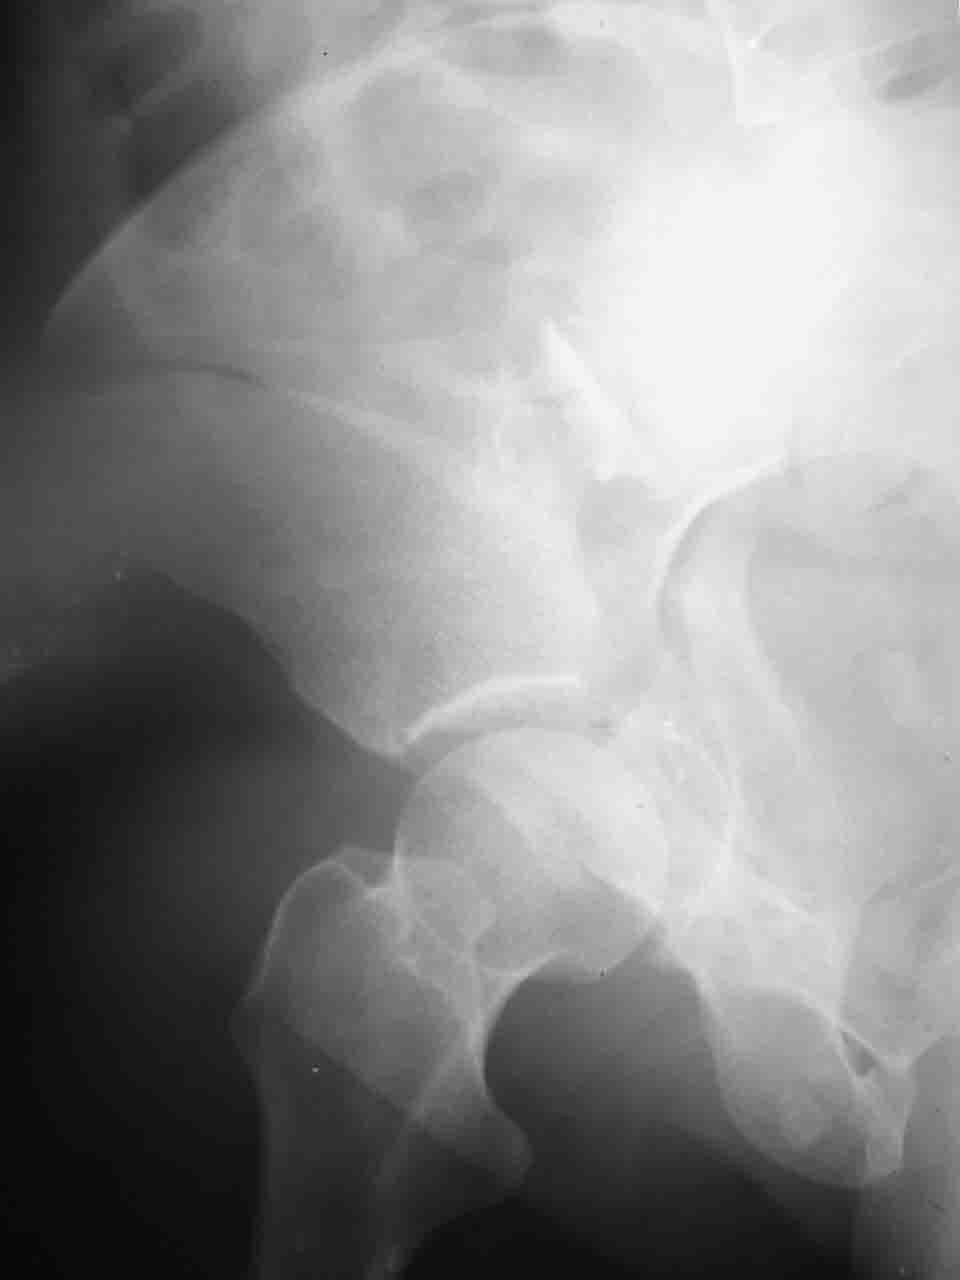

Логика подсказывает, что все-таки лучше иметь анатомически полноценную впадину, хотя ранее упоминалось состояние вторичной конгруэнтности и одно наблюдение у меня есть, когда у больного с полностью нарушенной анатомией впадины и подвывихом головки бедра кзади и кверху боли отсутствовали при относительно достаточном для стиля жизни больного объёме движений. Но это только одно наблюдение и кроме перелома впадины у этогобольного была и тяжелая ЧМТ в анамнезе. Основываясь на формулировке структуры ацетабулюм Э. Летурнеля - как перевернутой буквы Y, впадина для полноценной функции сустава должна иметь сферичность, соответствующую размеру головки бедра и если один из компонентов в дефиците, то функциональные последствия рано или поздно проявятся.

Сложностью, ассоциативностью характера перелома, я бы с радостью воспользовался мининвазивной перкутанной фиксацией винтами, но боюсь, что результат был бы ещё хуже, техникой непрямой репозиции перелома не владею, поэтому пытаясь получить анатомичную впадину приходится широко открывать, по крайней мере пока, а дальше буду пытаться уменьшать пространство...

Илеофеморальный доступ не совсем передний и сравнительно с илеоингвинальным, и Кохера-Лангенбека открывает весь наружный таз кроме самых передних отделов лонных костей, фиксацию которых я не ставил в задачу. Обширность диссекции, большая длительность операции и более высокий риск гетерооссификации - отрицательные моменты в обмен на возможность легче ориентироваться.

Вопрос доступа к вертлужной впадине при остеосинтезе задача не простая. Конечно, у Летурнеля и Тайла всё давно описано, нам остается только брать на вооружение. Но сами понимаете, что не бывает двух одинаковых ситуаций, поэтому в каждом случае вопрос решается сугубо индивидуально. Наша главная цель - восстановить анатомию с нанесением минимальной дополнительной травмы тазобедреннному суставу, думаю с этим никто не поспорит. Расширенный илиофеморальный доступ уж слишком травматичен (как сказал один коллега "таз лежит отдельно, больной отдельно").Стоит ли делать из пациента анатомический препарат для того чтобы легче ориентироваться. Да и нужно ли собирать всю "мозаику"? Мы применяли при таких операциях своеобразную операционную хитрость - сначала устраняли грубое смещение крыла под гребнем с фиксацией так называемой "плавающей" пластиной (временно фиксированной на двух винтах)- доступ или продлевали боковой, или делали небольшой дополнительный разрез над гребнем. Это позволяло устранить грубое смещение и захождение отломков тела повздошной кости, что значительно облегчало репозицию и остеосинтез впадины над сводом. Основное внимание конечно же уделяли нагружаемому задне-верхнему отделу. Сообщите ваш адрес, пришлю схемы и рентгенограммы.